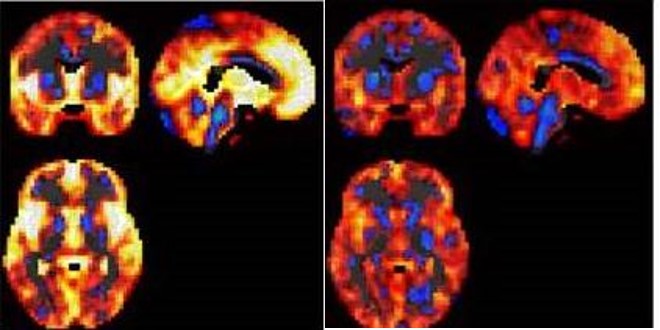

A través de la participación de 3.000 pacientes (853 con la enfermedad y 2.167 sanos),  el trabajo tuvo como objetivo diferenciar los individuos de un grupo u otro usando datos clínicos y neuroimagen analizados a través de técnicas de aprendizaje automático. En este caso particular, se buscaba la identificación de patrones a través del análisis de los datos clínicos y de neuroimagen que ayudasen a clasificar correctamente a los participantes en el grupo de pacientes con trastorno bipolar o en el de controles sanos.

De esta manera, se analizaron las imágenes cerebrales obtenidas mediante resonancias magnéticas junto con otras variables clínicas y sociodemográficas de interés (tratamiento, género, edad…) de los participantes. Los resultados demostraron un mayor rendimiento de clasificación del que se esperaría encontrar solo por azar, con un área bajo la curva (ROC-AUC) de 71, 49%. No obstante, los autores destacan que el nivel de precisión fue del 65, 23% inferior al umbral del 80% necesario para ser utilizado en la práctica clínica habitual.

El estudio realizado por el ENIGMA Bipolar Disorders Working Group, sin embargo,  constituye hasta la fecha la mejor aproximación para el empleo de técnicas de neuroimagen como exploraciones complementarias que ayuden a confirmar el diagnóstico clínico del trastorno bipolar. En la actualidad, el diagnóstico es puramente clínico, basado en la identificación de síntomas mediante una entrevista clínica llevada a cabo por un experto en salud mental, pero una parte de la investigación se dedica a estudiar marcadores biológicos, como cambios en zonas cerebrales, que puedan contribuir a mejorar el diagnóstico.